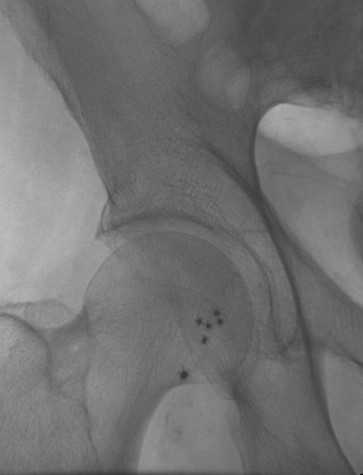

Celt ACD® allows multiple immediate re-sticks in calcified arteries.

6 Celt ACDs